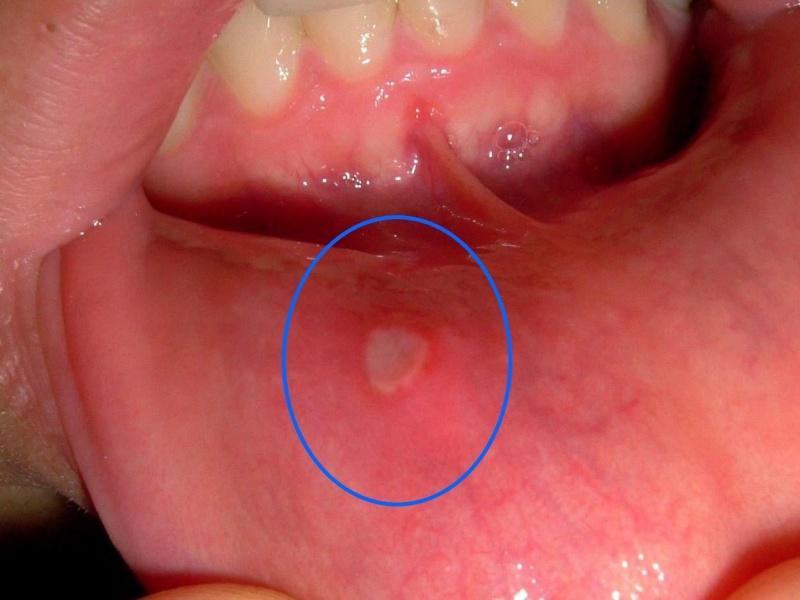

Семейство Herpesviridae включает более двухсот различных вирусов, которые распространены повсюду среди различных организмов. Однако только несколько из них могут заразить человека. Простой герпес — один из таких вирусов и может проявляться на лице, в полости рта или на гениталиях. В данной статье мы рассмотрим герпес, который появляется внутри губы (см. фото).

Герпес на внутренней стороне губ вызывает появление полых образований с жидкостью внутри, которые постепенно увеличиваются в размерах.